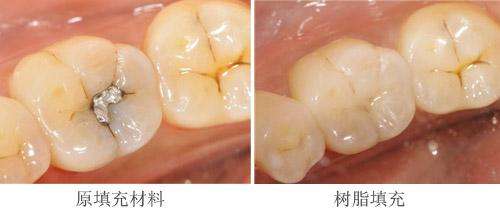

3、您选择的补牙材料:

补牙材料有银汞合金、树脂材料,其中银汞较便宜,但是不美观,而且在操作过程中银汞蒸汽对人体和对环境的污染。现在更常用的材料就是树脂,颜色和牙齿一样,很逼真、美观,强度也不错。>>>关于补牙材料直接咨询医生

康贝佳口腔:美国3M纳米树脂补牙

树脂是目前比较好的补牙材料,受到众多牙科患者的欢迎。采用的材料是有别于传统的真正的纳米树脂,它不仅提高了树脂的耐磨性和强度,同时具有杰出的抛光和抛光保持性,归结起来主要有4大优势:

3、色泽非常逼真

和传统补牙材料相比,纳米材料尤其能恢复牙齿自然外形,色泽逼真、有质感。